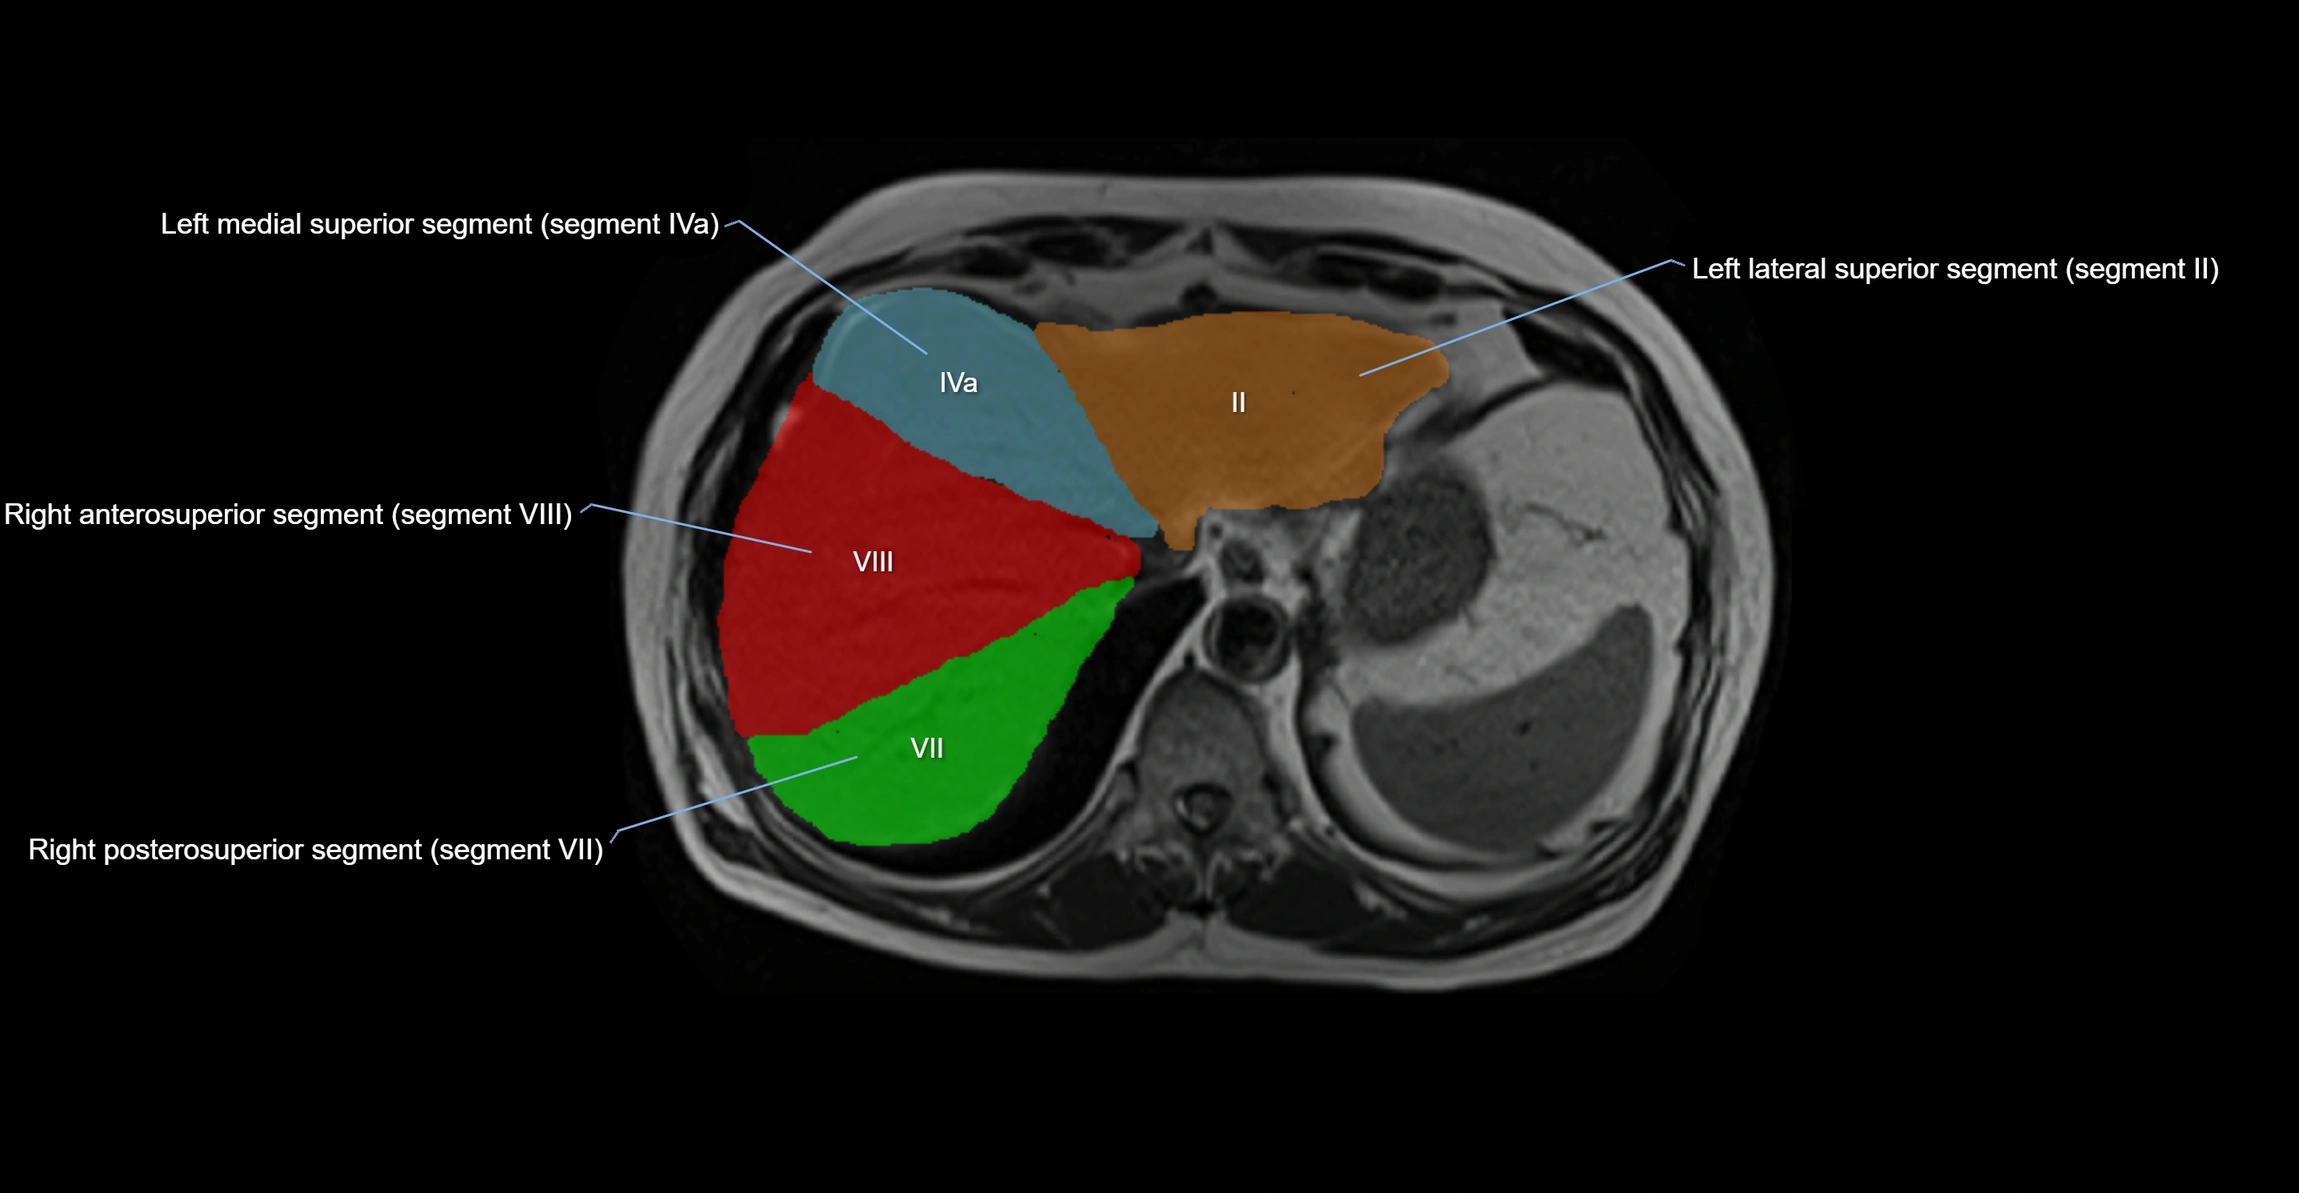

The caudate lobe of the liver is a distinct anatomical subdivision of the liver, designated as segment I in Couinaud’s classification. It lies on the posterior surface of the liver, between the fissure for the ligamentum venosum (left boundary) and the groove for the inferior vena cava (IVC) (right boundary). Superiorly, it is related to the posterior liver surface, and inferiorly it is separated from the left lobe by the porta hepatis.